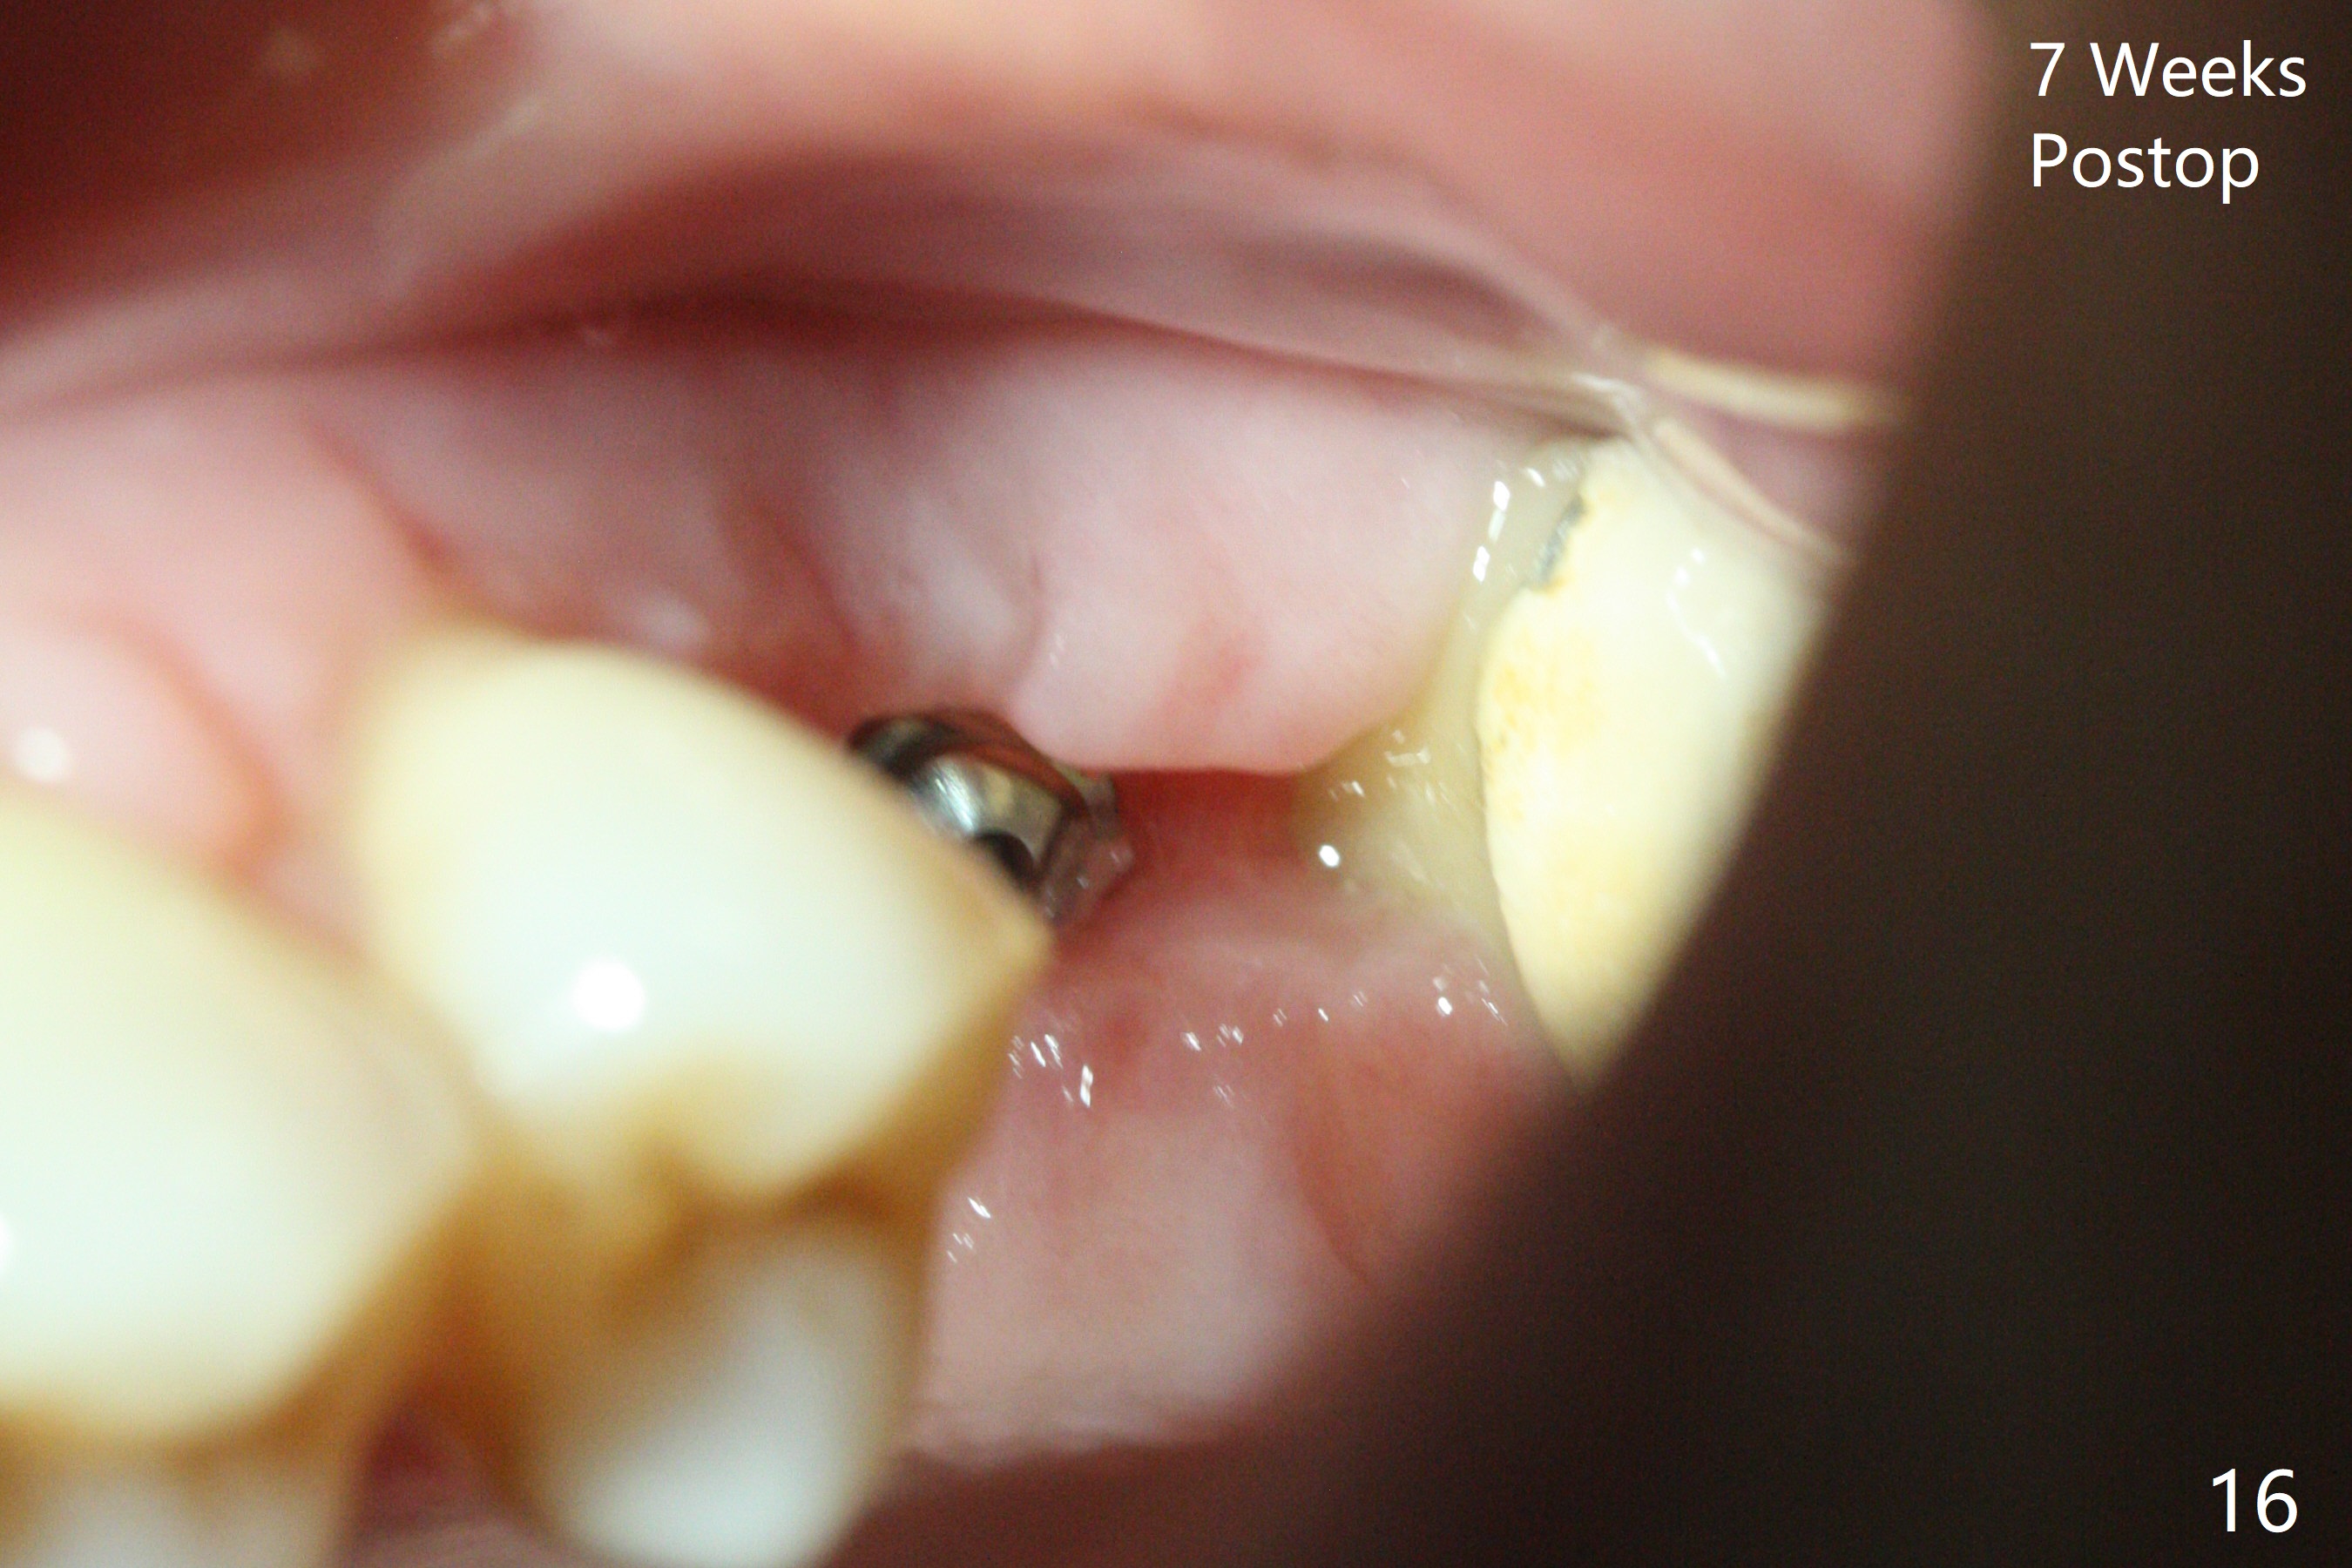

A 57-year-old woman complains of bad smell while use of water flosser between 11 and 21 months post cementation of implant crown at #14 (Fig.1,2). Bone loss is more obvious with CBCT (Fig.3,4), in spite of apparently normal gingiva around the implant after removal of the abutment and crown (Fig.5). In fact the buccal (B) gingiva is fragile with easy access to the underlying implant plateau. Following flap elevation, the bone loss is evident (Fig.6), but the implant plateau is slightly subcrestal (Fig.7 *). The exposed implant threads are covered with the 1st round of bone graft (Fig.8). After 2nd round of allograft (Fig.10-12) and collagen membrane, the flaps are approximated (Fig.9). The wound is covered by acrylic dressing. The latter is loose, but stays in place 1 week postop (Fig.13). Due to short neighboring teeth, the acrylic dressing is able to be removed with wiggling; it appears that the wound is healing (Fig.14). The dressing returns for another 2 weeks; some of the graft has been lost (Fig.15). The dressing does not return 7 weeks postop, since the wound is healing (Fig.16).